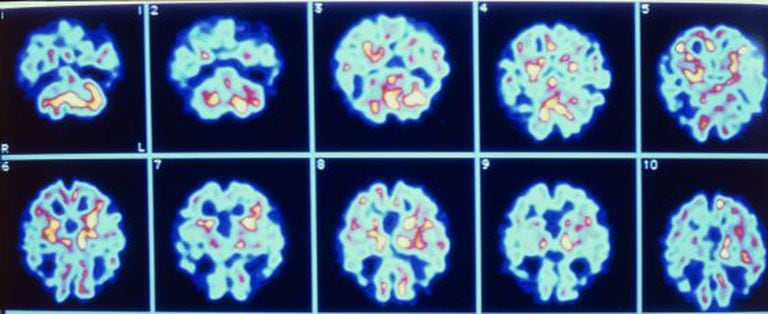

Um exame de sangue demonstrou a capacidade de diagnosticar com 90% de precisão o Alzheimer com três anos de antecedência. O trabalho, liderado por Howard Federoff, da Universidade de Georgetown (Washington DF), baseia-se nos níveis de 10 metabólitos lipídicos. A descoberta foi publicada na Nature Medicine.

O estudo fez o acompanhamento de 525 pessoas maiores de 70 anos durante cinco anos. Foram feitas diversas comparações e verificou-se que as pessoas que desenvolveram Alzheimer ou problemas cognitivos mais leves tinham níveis mais baixos destes 10 fosfolipídios.

A relação é puramente estatística, já que Federoff admite que não sabe nem sequer de onde vêm essas moléculas, embora se saiba que estão presentes nas membranas celulares. Por isso, pressupõe-se que o que estão mostrando é um rompimento dos neurônios, unida ao deterioramento cognitivo.